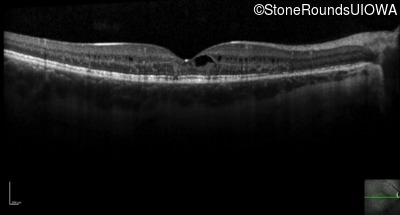

Optical Coherence Tomography - Right - 20/40 +1

Exemplar / OCT Stack

OCT Stack